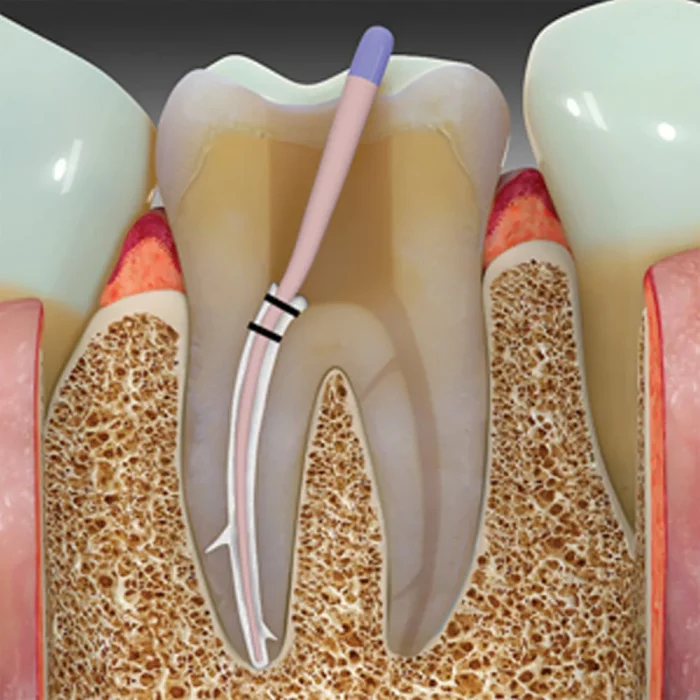

- Uses cold single cone or cold lateral condensation

Septodont’s BioRoot™ RCS is a revolutionary bioactive mineral root canal sealer that harnesses the power of their patented Active Biosilicate Technology. With high mineral purity and a monomer-free composition, BioRoot™ RCS ensures optimal biocompatibility and reduces the risk of adverse reactions. It promotes hydroxyapatite formation at the tooth-sealer interface, aiding in the mineralization of the dentinal structure for enhanced long-term stability. The sealer exhibits antimicrobial properties, effectively combating bacterial growth and minimizing the chances of reinfection. Its resistance to microleakage contributes to a durable and reliable seal. Additionally, BioRoot™ RCS provides excellent radiopacity for clear post-operative assessment. Its easy handling and retractable properties, simplifying application during procedures. Notably, BioRoot™ RCS is MR-safe, posing no risks or interactions within magnetic resonance imaging environments. It is also safe for use during pregnancy, offering added peace of mind. Ideal for the permanent root canal filling in a variety of cases, including vital or necrotic pulp situations and retreatment procedures, BioRoot™ RCS can be utilized with either the single cone technique or cold lateral condensation.

- BioRoot™ RCS provides permanent root canal filling with gutta-percha points in various pulp cases and retreatments.